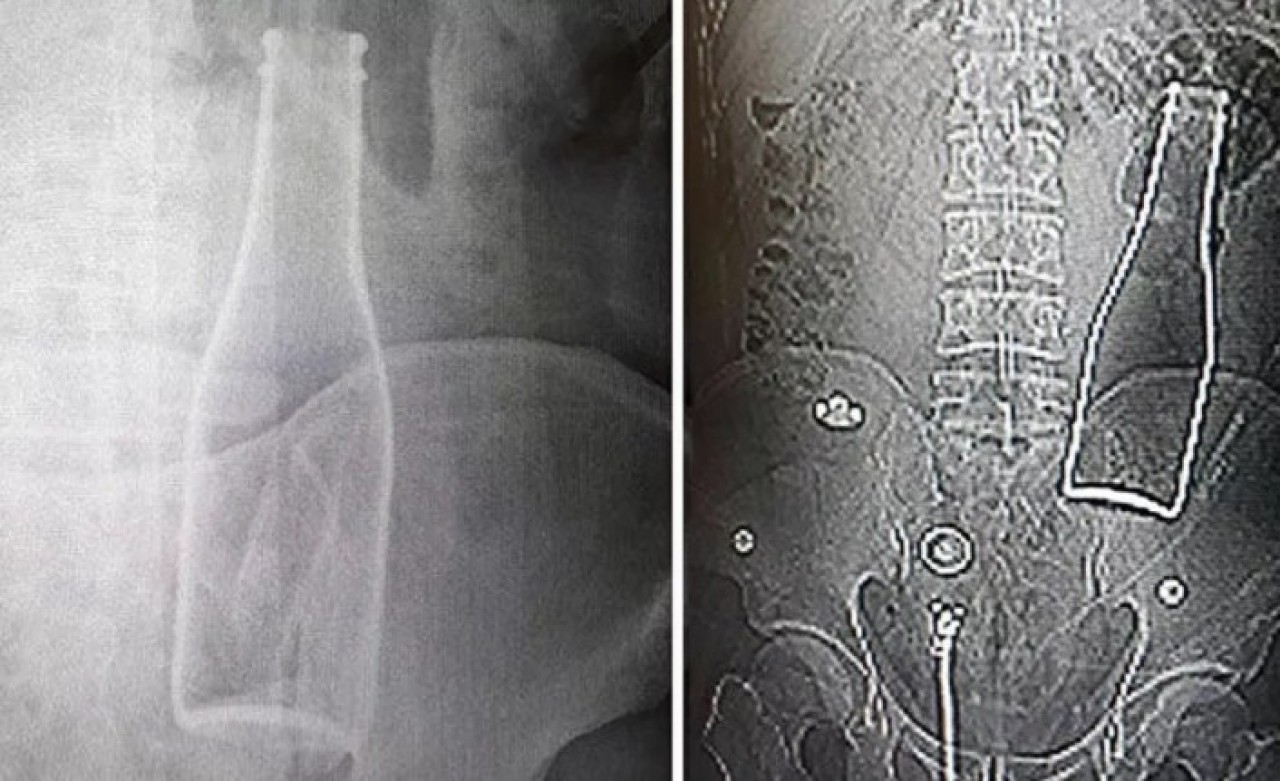

Bunun üzerine röntgen filmi çekilen gencin kalın bağırsağında şişe olduğu görüldü. Makattan girdiği belirlenen şişe, yaklaşık bir saat süren ameliyatla çıkarıldı.